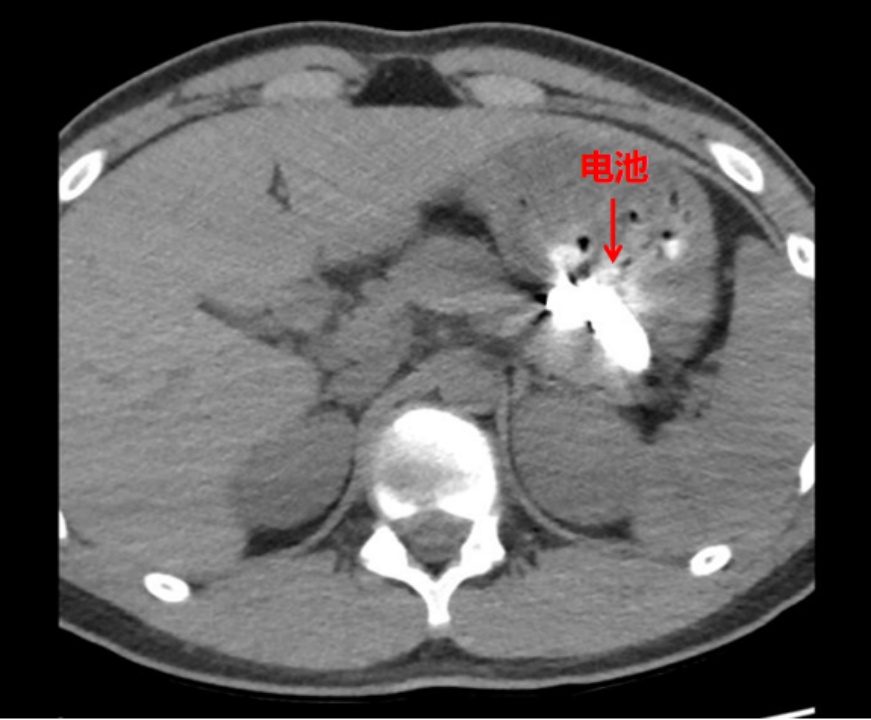

“医生,快立刻给他做胃镜!不然电池就腐蚀了!”面对家属立刻做胃镜的请求,接诊医生并未贸然操作,而是先对患者进行了全面评估。“吞服异物后不能贸然进镜,必须先明确异物位置和身体损伤情况。”医生解释,如未判断清楚电池所在部位及是否存在漏液腐蚀,盲目操作可能加重损伤,甚至引发食管或胃壁穿孔,风险极高。随后,医护团队迅速为患者完善CT检查,明确异物位置。

影像结果显示,两枚电池均位于胃腔内。但患者胃内存在大量未消化食物,电池被掩埋其中,胃镜视野严重受限。同时,由于禁食时间不足,无法立即进行麻醉,只能在患者清醒状态下进行胃镜操作,进一步增加了手术难度与患者不适感。